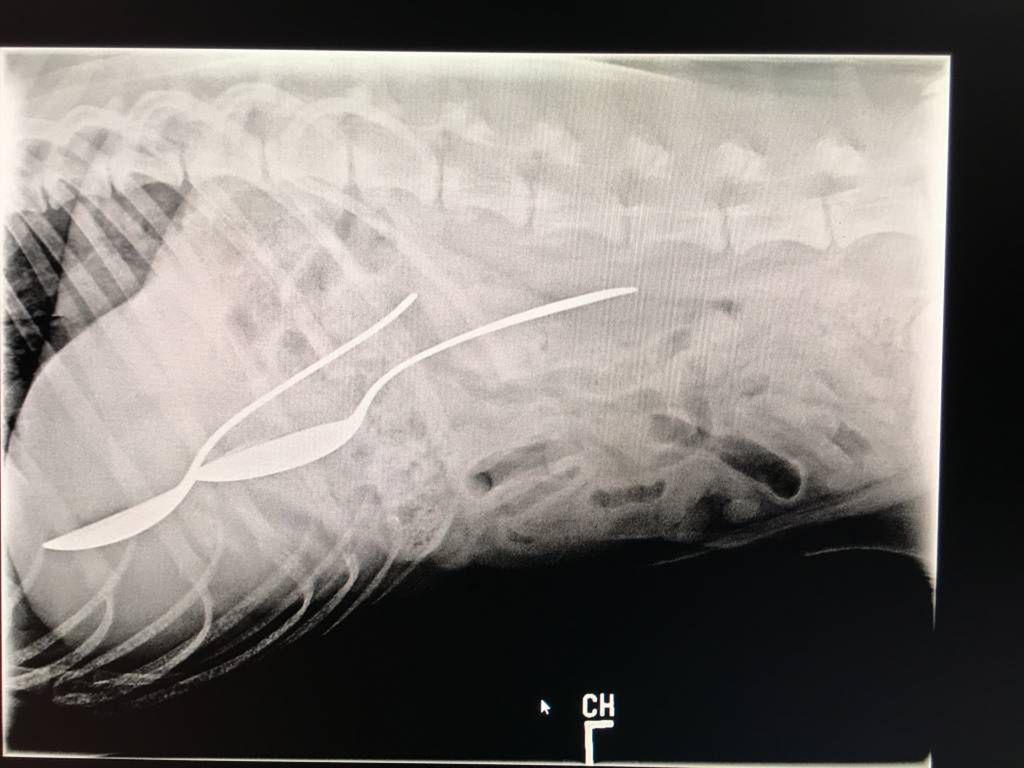

Źródło zdjęć: © veterinarypracticenews.com / They Ate What?

© veterinarypracticenews.com / They Ate What?

© Veterinary Practice News/Lauren Flanagan, DVM, of Pepperell Veterinary Hospital in Pepperell, Mass.

Zwyciężyła półroczna angielska buldożka Leia. Właściciel dał jej do obgryzania 12-cm kość. Nie przewidział, że suczka połknie ją w całości.